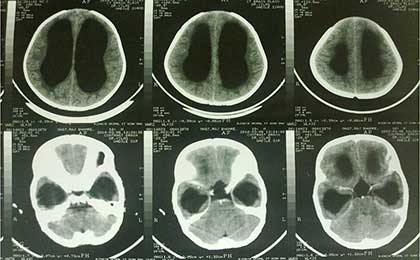

Hydrocephalus With Cerebellar TB Granuloma

Post Shunt with Cerebellar TB